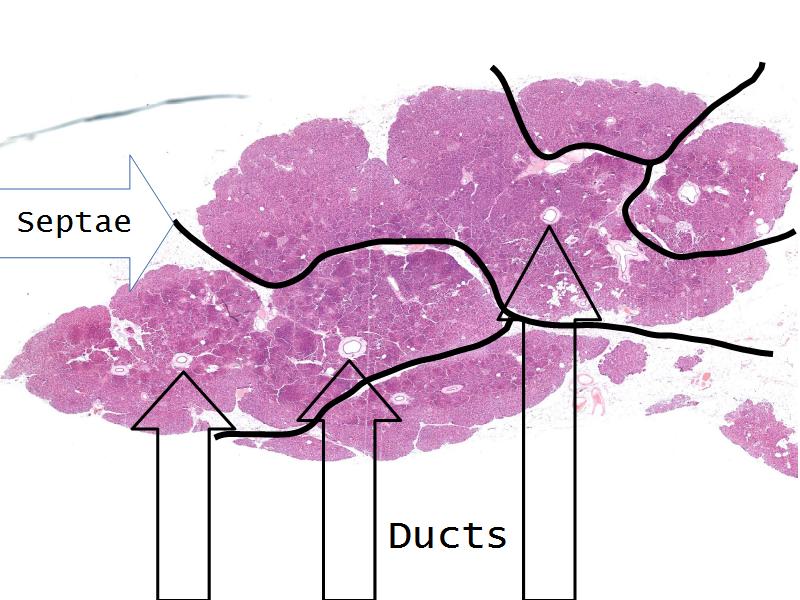

- Pancreas

- C3: Pancreas

- C3: Pancreas = glucagon, insulin, somatostatin, pancreatic polypeptide

- F4: Alpha cells = pancreas

- Slide 50: Pancreas